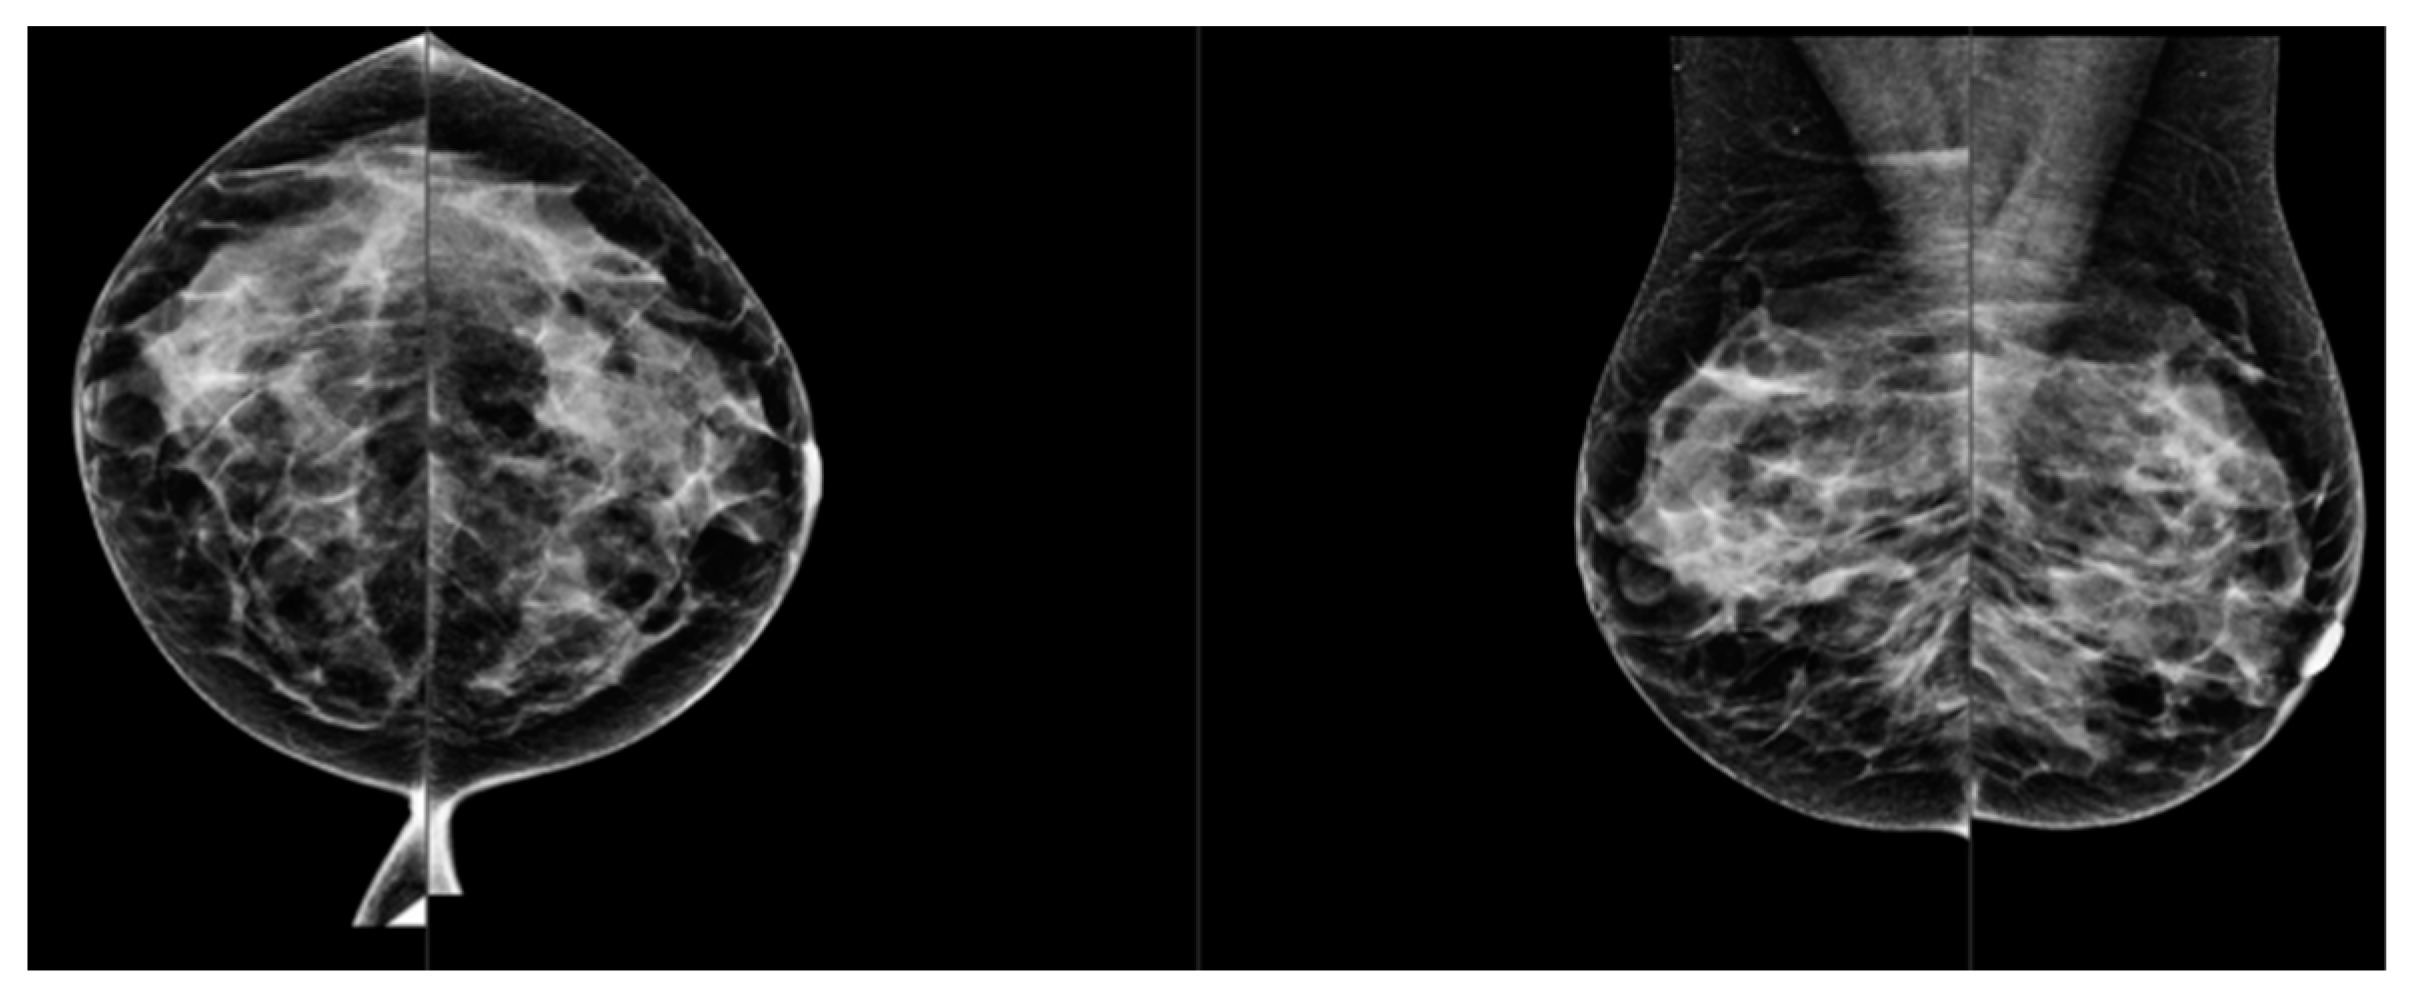

Comparison of Visual and Quantra Software Mammographic Density Assessment According to BI-RADS® in 2D and 3D Images

2. Materials and Methods

2.2. Image Acquisition

2.3. Software for Automatic Breast Density Assessment

| BI-RADS Category: | Reader 1 (R1) | Reader 2 (R2) | Mean R1-R2 | Quantra Software (R3) |

| A | 1646 (33%) | 1538 (30%) | 1592 (32%) | 673 (13%) |

| B | 2241 (45%) | 2364 (48%) | 2303 (46%) | 2131 (43%) |

| C | 915 (18%) | 891 (18%) | 903 (18%) | 1728 (34%) |

| D | 178 (4%) | 179 (4%) | 179 (4%) | 477 (10%) |